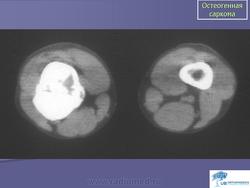

Остеосаркома (синонимы: центральная остеосаркома, остеофибросаркома, остеохондросаркома, медуллярная остеосаркома) - злокачественная опухоль, при которой новообразованная кость или остеоид продуцируются непосредственно самими опухолевыми клетками. Среди всех сарком кости, остеосаркома встречается наиболее часто и локализуется в длинных костях скелета.

Рентгенологическая картина. Типичной картиной является наличие очага смешанной деструкции кости с разрушением кортикальной пластинки и формированием мягкотканного компонента опухоли. В процессе роста опухоли, периост приподнимается или отслаивается от коркового слоя, это вызывает новое костеобразование, обычно проксимальнее основного узла, данное явление получило название козырька Кодмана. Зона поражения на рентгеновском снимке имеет различную плотность, а характер матрикса часто облаковидный. КТ и МРТ могут играть важную роль в определении распространенности опухолевого процесса. Радионуклидное сканирование скелета выявляет «skip» метастазы, многоузловые опухоли, системное поражение. В ряде клиник принято использовать артериографию, так как остеосаркомы - гиперваскуляризованные опухоли.